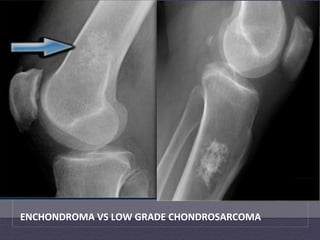

ENCHONDROMA  VS  LOW  GRADE  CHONDROSARCOMA